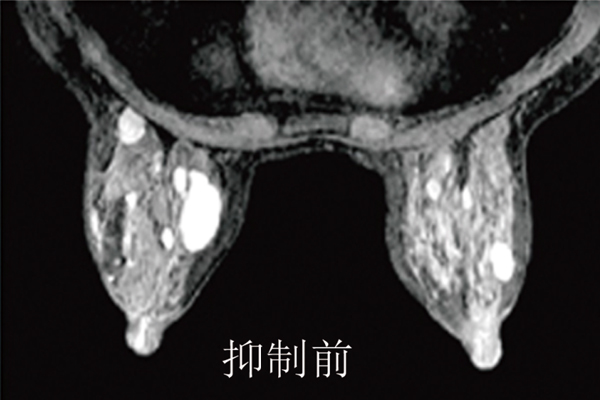

奧洛瑞專(zhuān)利的RODEO脈沖序列,具有充分的脂肪影像抑制和乳腺管影像抑制,能有效地減少影像的偽影,尤其是心臟跳動(dòng)與呼吸所產(chǎn)生的移動(dòng)偽影,因此能產(chǎn)生更加清晰的影像,提高病灶的檢測(cè)能力。